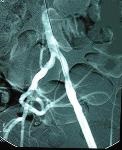

Perkutánní transluminální angioplastika (PTA) + zavedení stentu pánve a dolních končetin

PTA je perkutánní (přístup přes kůži) léčebná metoda, kdy se pomocí balónku či výztuže (stentu) rozšiřuje zúžený či uzavřený úsek tepny. Výkonu vždy musí předcházet podrobné vyšetření cév – angiografie, CT nebo MR angiografie.

Nejčastější indikací je zprůchodnění postižení tepny a obnovení dostatečného krevního zásobení postižené oblasti. Metodu nelze použít u všech pacientů, o vhodnosti tohoto výkonu se rozhoduje na základě angiografického vyšetření, které je konzultováno s cévními specialisty z oboru chirurgie a interny.

PTA se provádí v místním znecitlivění a je to výkon nebolestivý. Do tepny obvykle v třísle se zavede jehla, přes kterou zavedeme vodič a kterým pronikneme skrz postiženou oblast až do „zdravé“ tepny. Poté do postižené oblasti zavedeme speciální balonkový dilatační katetr (balónek) a „nemocnou“ tepnu ošetříme buď pouze roztažením balonku nebo zavedením stentu, který drží požadovaný průměr ošetřované tepny. Současně se získávají snímky léčené oblasti před a po léčbě pomocí PTA. Na konci výkonu lékař odstraní zaváděcí pouzdro, balonek a vodič (instrumentárium) a místo, kudy bylo instrumentárium zavedeno se stlačí na dobu nezbytně nutnou k zástavě krvácení z tepny. Délka výkonu je zcela individuální v závislosti na lokalizaci a závažnosti postižení tepenného systému. Délku výkonu upřesní výkon provádějící intervenční radiolog.